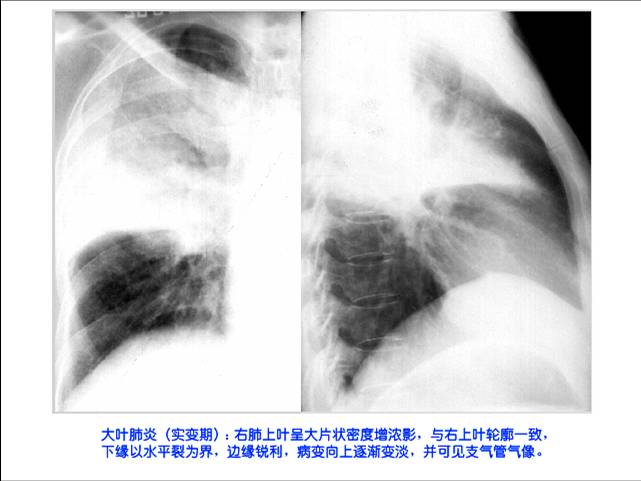

照片名称:大叶肺炎-突变期